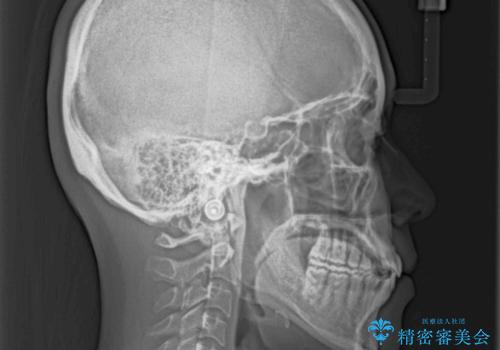

オープンバイトでかみにくい インビザラインによる矯正治療

- 前歯の上下スペースによる食べにくさを気にして来院された患者様です。

インビザラインにより上下の前歯の隙間を閉じていくこととしました。

上下の奥歯を圧下させるようにすることで、前歯を接触させるように計画しました。

上下の隙間に舌が入り込むことがオープンバイトの原因であったため、舌の筋肉のトレーニングも並行して行い、後戻りの抑制を図りました。